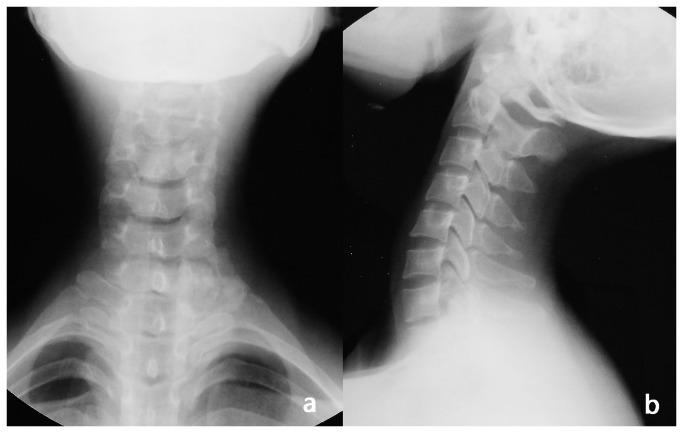

From June 2006 to July 2011, 18 patients with spinal osteoblastoma treated surgically were analyzed retrospectively. There were 11 males and 7 females with an average age of 27.5 years(range, 16-38 years). The tumors were located at C5 in 7, C6 in 6, C7 in 3, C6-T1 1 in 1 and T11 in 1. Based on WBB classification, 16 were 1-3 or 10-12 and 2 were 4-9 and 1-3. 18 operations had been performed with en bloc resection. A posterior approach was used for 16 patients, and a combined posterior and anterior approach was used for 2 patients. Reconstruction using instrumentation and fusion was performed using spinal instrumentation in 13 patients. We used visual analogue scales (VAS) to evaluate the change of pain before and after the operation, and the McCormick System to assess functional status of the spine. Imaging test was used to review the stability and recurrence rate of spine cord, and the confluence of graft bones.

Spinal osteoblastoma has its own specific radiographic features. There is some recurrence in simple curettage of tumor lesion. The thoroughly en bloc resection of tumor or spondylectomy, bone fusion and strong in Ter fixation are the key points for successful surgical treatment.